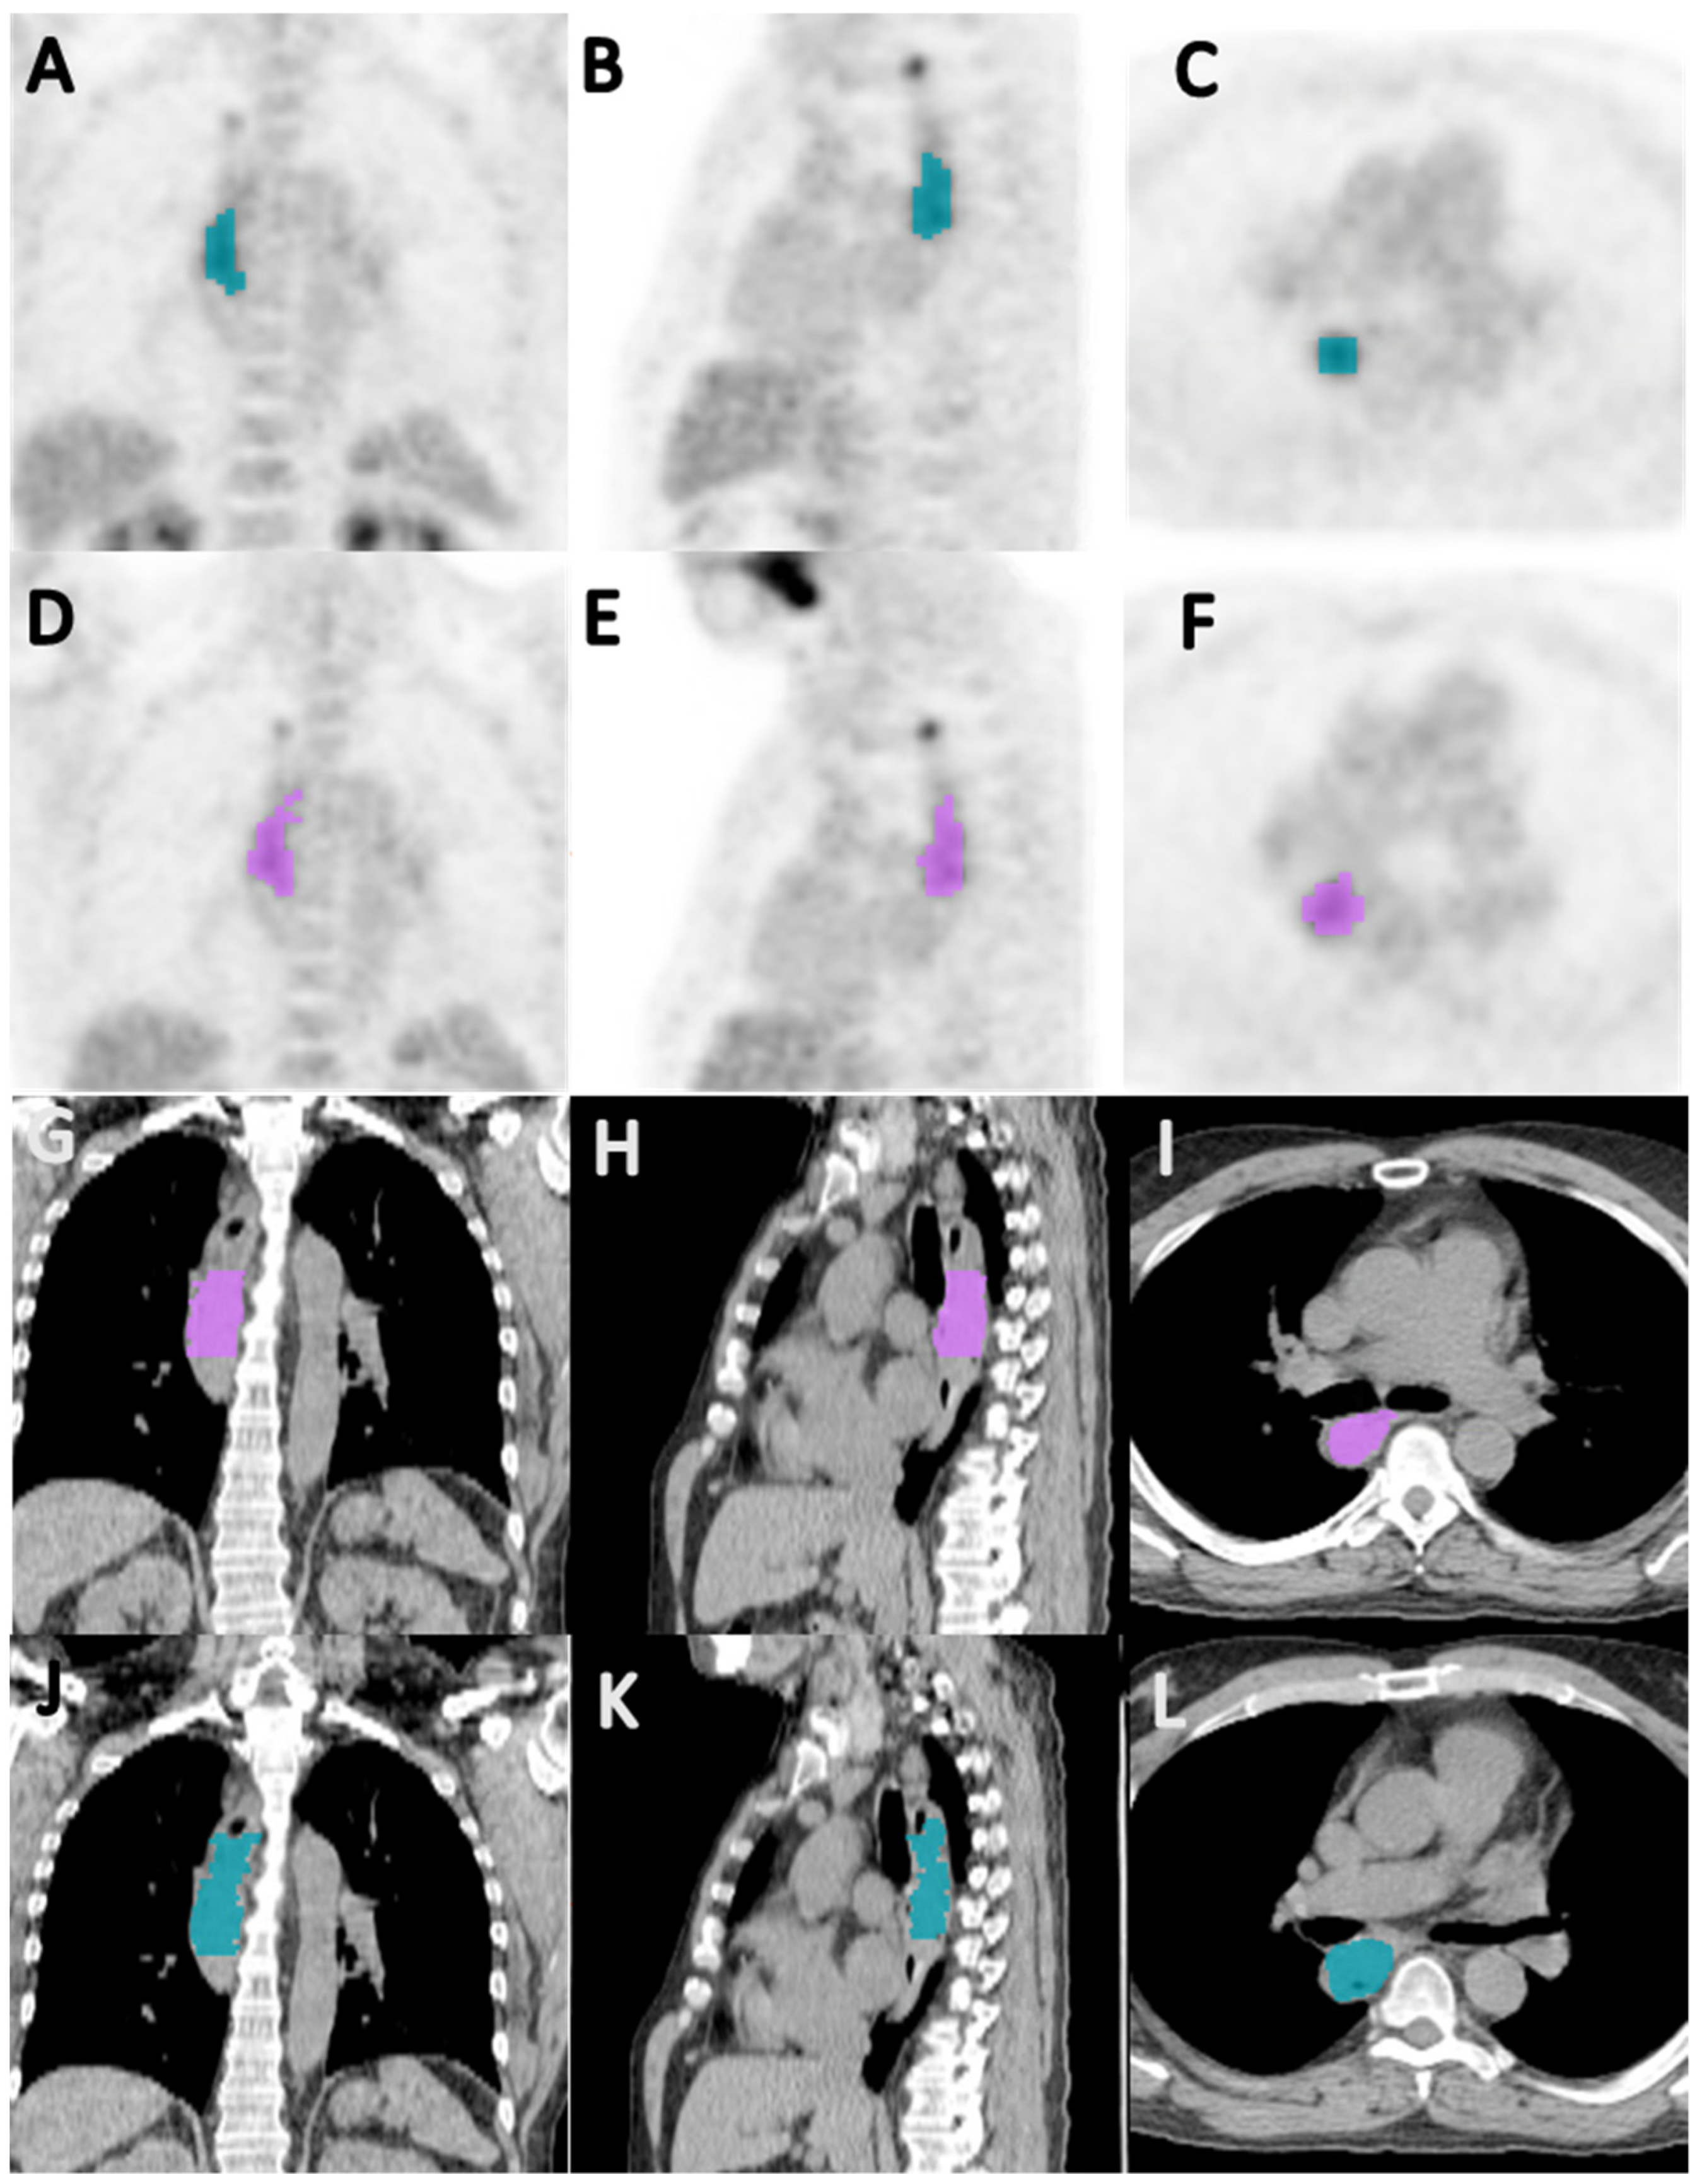

2.3. Image Acquisition and Segmentation